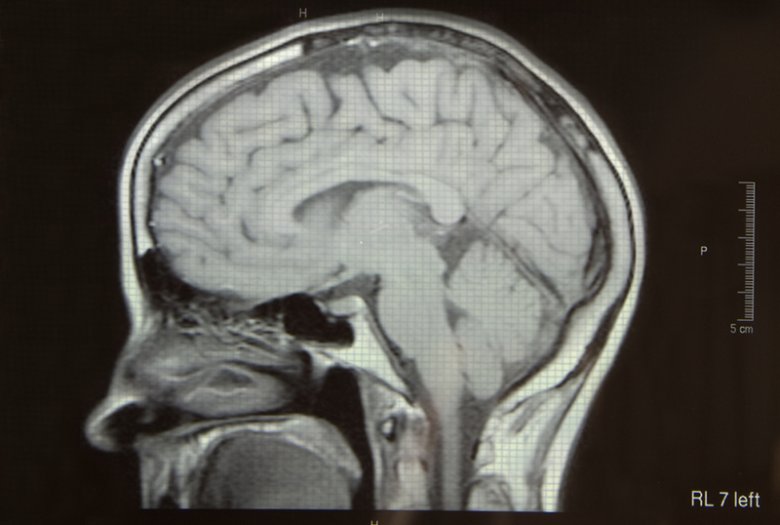

Móżdżek to struktura ośrodkowego układu nerwowego, która odpowiedzialna jest za koordynację ruchową i zachowanie równowagi ciała. Najnowsze badania sugerują, iż móżdżek.

Móżdżek - budowa, funkcje, choroby i uszkodzenia. Konsultacja merytoryczna: Lek. Aleksandra Witkowska. Móżdżek jest największą częścią tyłomózgowia (waży około 150.